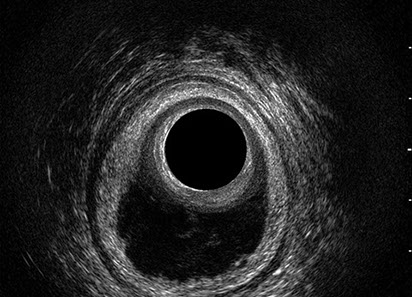

L’ecografia transanale è un esame diagnostico per immagini che consiste nell’introduzione di un trasduttore ad ultrasuoni. Le immagini qualitativamente migliori del canale anale sono ottenute usando un trasduttore rotante, montato in un manipolo rigido, che fornisce un’immagine a 360°. Con le apparecchiature più moderne è anche possibile ottenere immagini tridimensionali.

L’ecografia transanale permette di distinguere la sottomucosa che riveste il canale anale, lo sfintere anale interno, e lo sfintere anale esterno.

Le principali indicazioni all’esecuzione di tale esame sono lo studio dell’integrità delle strutture muscolari nei casi di incontinenza fecale, lo studio topografico dei processi settici perianali (ascessi e fistole) e lo studio dei processi proliferativi epiteliali (carcinoma anale).